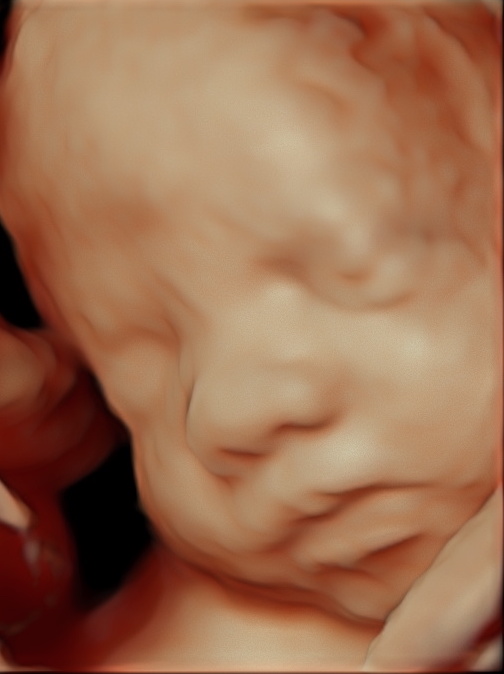

Echoburo Babywatch is een gespecialiseerde en ervaren echopraktijk in medische echo’s en pretecho’s. Met ruim 25 jaar echoscopie ervaring en de nieuwste apparatuur laten wij de mooiste beelden zien van jullie baby!

Daarnaast krijg je bij Echoburo Babywatch altijd foto’s mee naar huis, ook als julie voor een medische echo zijn langsgeweest.